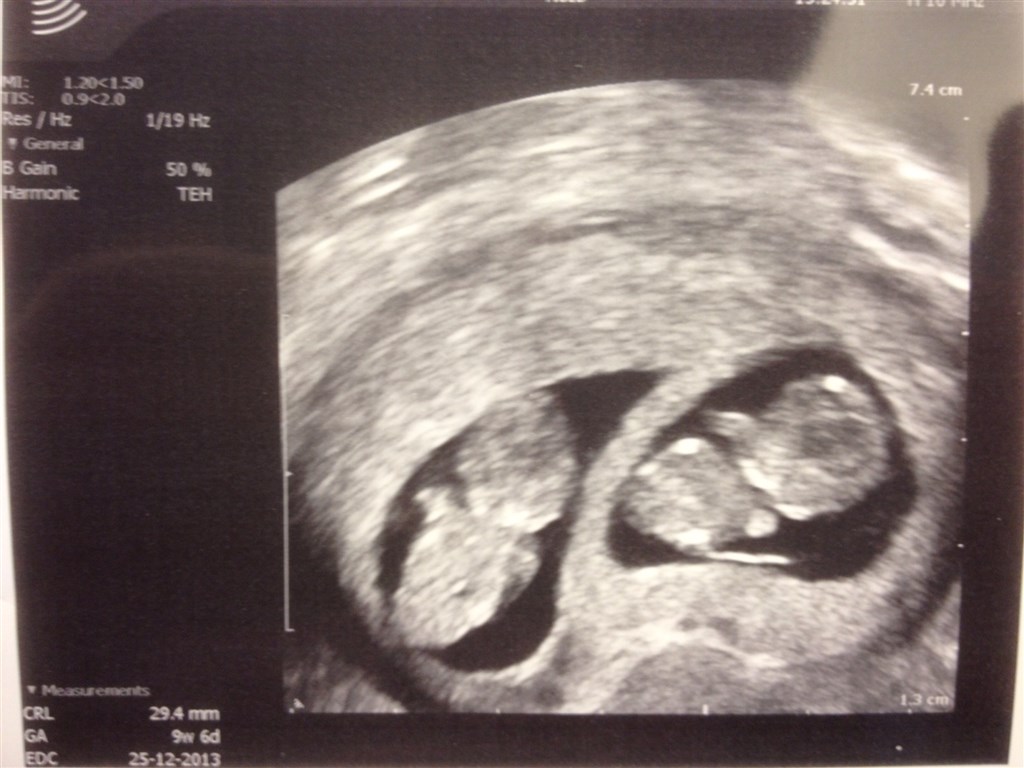

Og bøllerne..

Vedhæftede fotos (klik for at se i fuld størrelse)